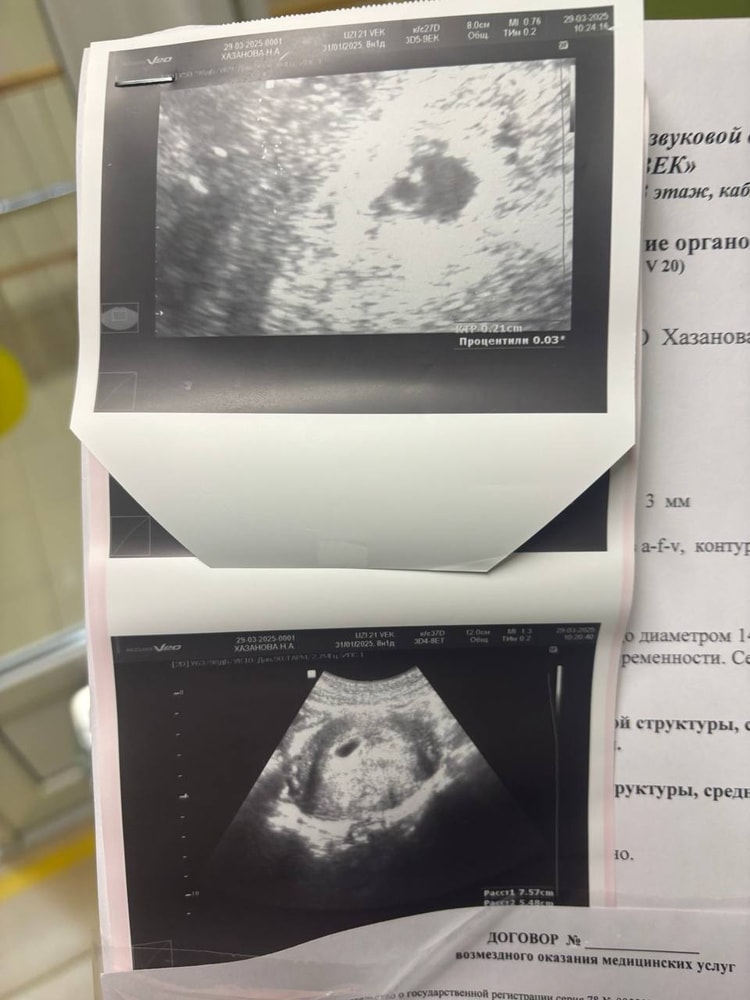

Вот на снимке хорошо видно, колечко, это ЖМ, а точечка на нем, это эмбрион. Срок тут 6+3

если 3,2, то рано, у меня вот такой был на сроке 6 недель.